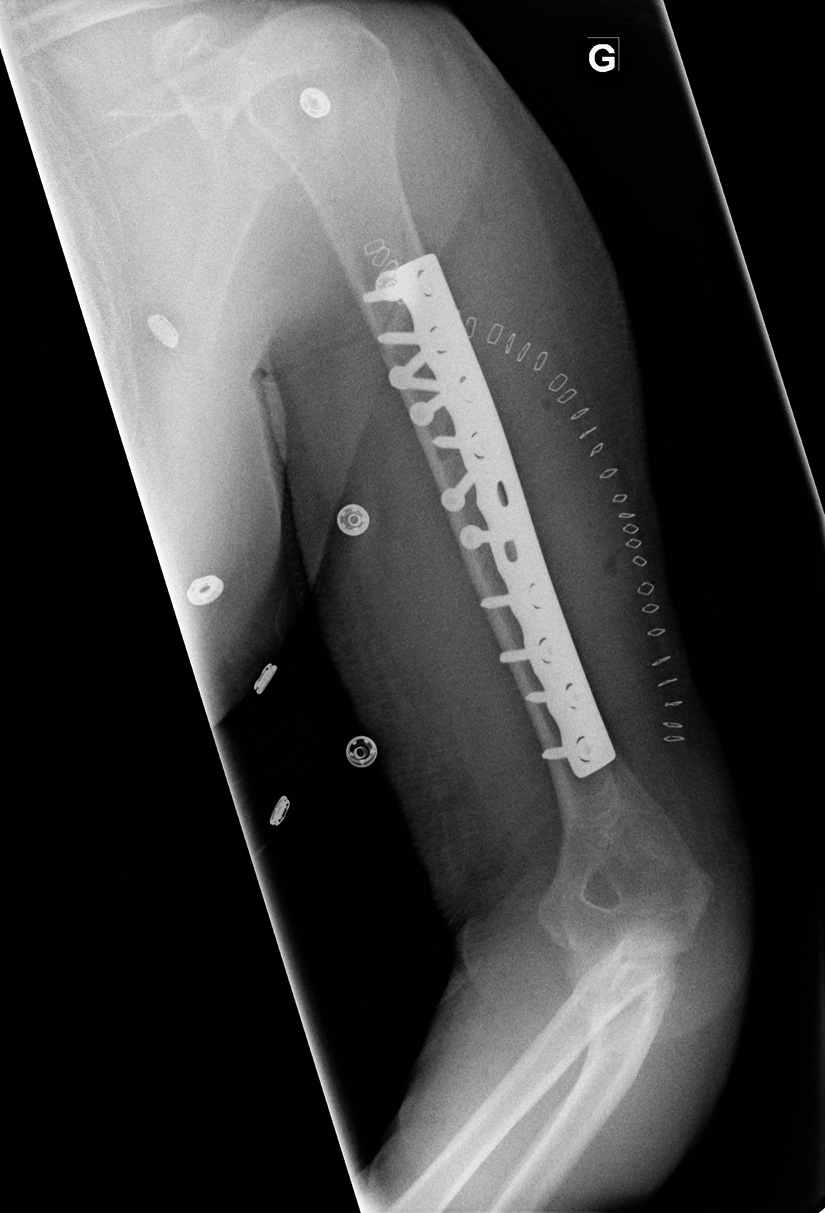

59-year-old male:

Postoperative control of a torsion trauma of the upper limb.

Humeral shaft fracture

Postoperative radiograph following the open reduction and internal fixation of a comminuted fracture of the humeral shaft. The fracture is reduced to an anatomic position and 4 interfragmentary screws are installed to secure the reduction.

In addition to the 4 interfragmentary screws, a plate and its screws are then added to strenghten the fixation.

Orthesis

Proctective orthesis in place.

Staples

Metallic staples in place for skin closure.